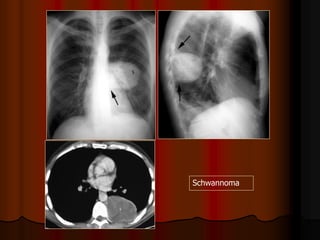

31-Oct-1435

A.J.Chandrasekhar,M.D.Chest X-ray Atlas.

HILUM OVERLAY SIGN: TERATOMA

Thymoma

Schwannoma